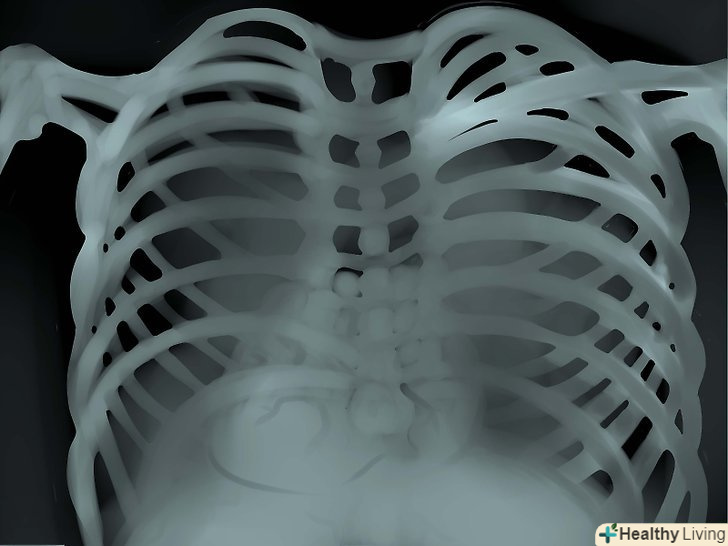

Кістки. уважно подивіться, чи немає де пошкоджень і травм кісток. Розмір, форму, контур і колір кісток необхідно примітити - все це цінний діагностичний матеріал, на підставі аналізу якого можна виявити безліч захворювань і патологій.